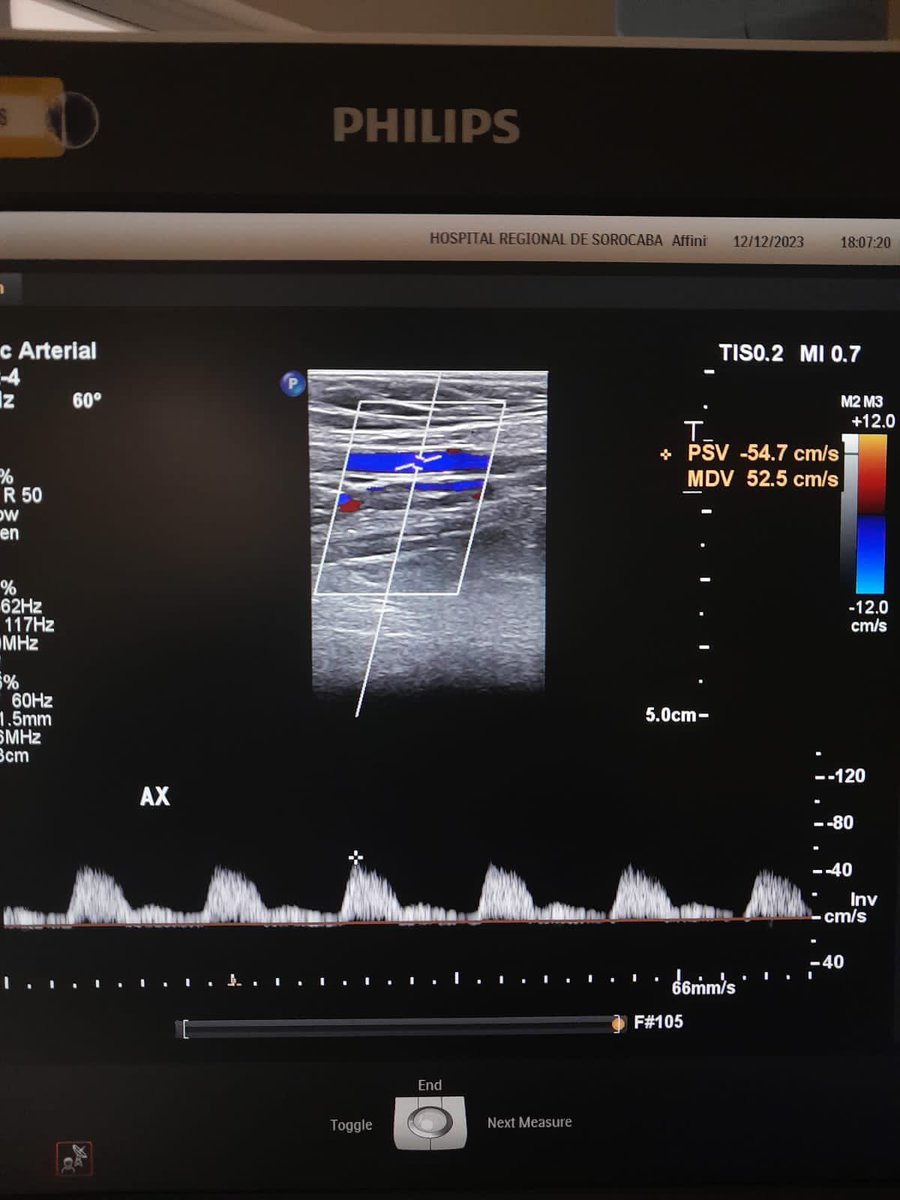

48y, ílio-popliteal dvt, symptomatic. angiographic control after ClotTriever. No thrombolytic, no cti needed. @InariMedical